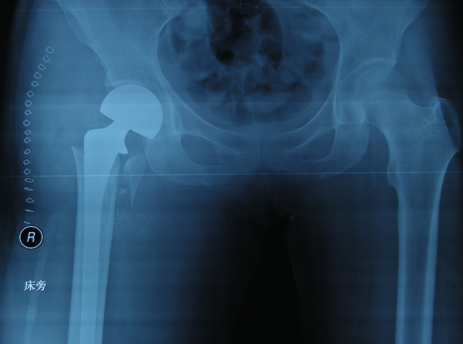

病理性骨折就是在某些疾病基础上出现的骨折。这其中发生率最高的原发疾病是结核、肿瘤和骨质疏松。它与单纯外伤性骨折不同,病理性骨折的骨头预先被某些病侵蚀、破坏、蛀空,再遇到轻微的外力,甚至没有外力只因自身的重力作用就可以自发骨折。大多数不需要CT、磁共振等高费用检查,只需拍X线片就可以大致判断出病变的性质、范围、破坏程度以及可能发生病理性骨折的危险性。

股骨转子间病理性骨折是现代老年患者常见的病理性骨折,多数有肿瘤类疾病病史。现代医学手术为治疗首选,应用特制肿瘤假体,可以很好的解决因骨质被破坏而引起的骨质缺损及关节周围重建等问题,早期离床下地活动,减少长期卧床的并发症发生,延长有效寿命,提高生活质量。

患者中老年女性,67岁,入院前在家中仅为拾取东西,在下蹲过程中即听到右髋部有响声,随即倒地。当时患者无任何外力影响,因伤后右髋部疼痛,关节活动受限,而到我院就诊,门诊收入院治疗。

X线及CT提示右股骨转子间骨质破坏,可明确诊断为右股骨转子间病理性骨折。我科行手术治疗,给予肿瘤假体置换,并行关节周围重建,手过程非常顺利。

术后仅2周左右,右髋关节床上活动基本达到正常,3周时逐渐下地,在助行器及家人协助下行走,未感到明显不适。1个月基本完全康复,生活达到自理,患者及家属对于治疗效果感到非常满意。